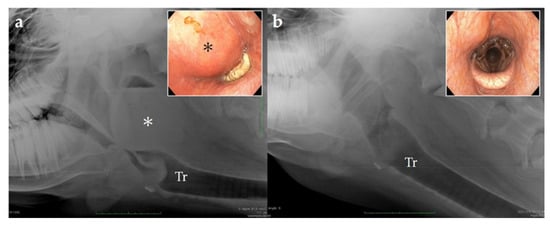

Figure 3. Endoscopic view of the dorsal aspect of the nasal passage and the upper respiratory tract with a retropharyngeal mass. (a) Pus-like material adherent to the dorsum of the nasal passage; (b) mass (*) in the pharyngeal region obstructing the airways.

3.4. Endoscopy

Endoscopy (9.2 mm video scope, VES Be-one, Olympus Medical Systems Corp., Tokyo, Japan) of the upper airways was performed without sedation. It showed pus-like deposits on the dorsal nasal septum, hyperemia, and edema of the dorsal pharynx. The swelling was pronounced, obstructing the airways and preventing further progression of the endoscope to examine the larynx (Figure 3).

Figure 6. Lateral radiography of the pharyngeal area and endoscopic view via the nasal cavity. (a) Day of admission; (b) sixteen days after the surgery. Tr: trachea; *: abscess.